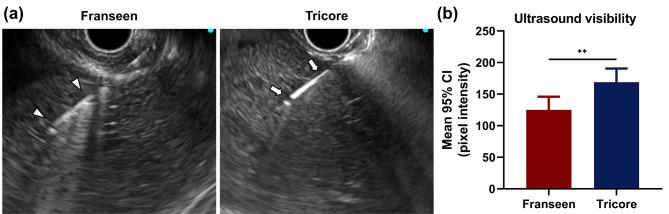

Endoscopic ultrasound-guided fine needle biopsy is an effective method for obtaining tissue samples from various organs; however, challenges such as inadequate specimens persist. This study compared a newly designed Tricore needle with a Franseen needle for endoscopic ultrasound-guided fine needle biopsy of porcine liver. Both needles were tested on four male Yorkshire pigs. Specimens were obtained with an 100% (36/36) success rate with no procedure-related adverse effects. The Tricore needle experienced significantly less resistance during puncture than Franseen needle (3.83 vs. 5.97 N, P < 0.001) and better ultrasound visibility (168.97 vs. 125.04, P = 0.004). The Tricore needle also achieved faster specimen acquisition time (48.94 vs. 59.90 s, P = 0.038), larger total specimen area (6.67 vs. 4.68 mm, P = 0.049), fewer fragments (23.94 vs. 31.94, P = 0.190), lager fragment area (0.28 vs. 0.15 mm, P < 0.001), and more the number of complete portal tracts (15.44 vs. 9.33, P = 0.017) compared to the Franseen needle. The newly designed Tricore needle showed enhanced procedural performance and specimen quantity and quality compared to commercially available Franseen needle. Although further clinical studies are required, the Tricore needle may represent a favorable option for endoscopic ultrasound-guided fine-needle biopsy procedures.

经内镜超声引导细针活检是一种从各种器官获取组织样本的有效方法;然而,仍然存在标本不足等挑战。本研究比较了一种新设计的 Tricore 针和 Franseen 针在猪肝脏经内镜超声引导细针活检中的应用。两种针均在 4 只雄性约克夏猪上进行了测试。均以 100%(36/36)的成功率获得标本,无与操作相关的不良事件。Tricore 针在穿刺过程中的阻力明显小于 Franseen 针(3.83 比 5.97 N,P<0.001),且超声可视性更好(168.97 比 125.04,P=0.004)。Tricore 针还获得了更快的标本采集时间(48.94 比 59.90 s,P=0.038)、更大的总标本面积(6.67 比 4.68 mm,P=0.049)、更少的碎片(23.94 比 31.94,P=0.190)、更大的碎片面积(0.28 比 0.15 mm,P<0.001),以及更多的完整门脉道(15.44 比 9.33,P=0.017)。与商用的 Franseen 针相比,新设计的 Tricore 针在操作性能、标本数量和质量方面均有改善。尽管还需要进一步的临床研究,但 Tricore 针可能是经内镜超声引导细针活检的一种有利选择。